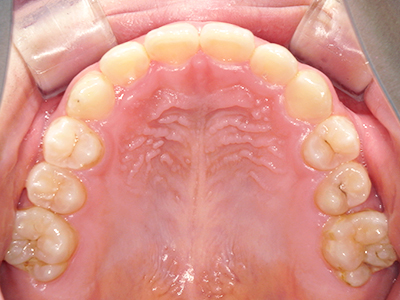

ないき歯科クリニックでは、上あごの成長不足を補い、鼻呼吸を獲得しつつ歯列を整え、将来のお口をより健康な状態にすることをゴールに定める矯正治療をおこなっています。

【4】矯正治療

矯正装置を装着し、調整しながら少しずつ歯を移動させ、歯並びを整えていきます。